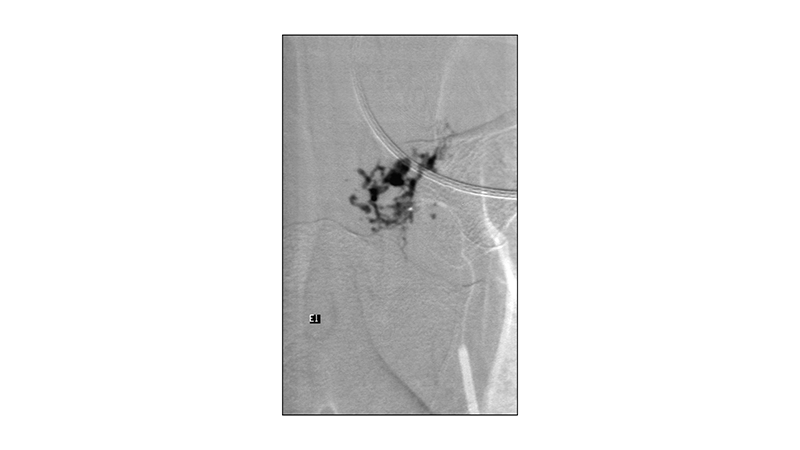

Εικόνα 4: Υπερεκλεκτικός καθετηριασμός του τροφοφόρου κλάδου που αιματώνει το σπονδυλικό σώμα.

Εικόνα 5: Ακολουθεί εμβολισμός με κυανοακρυλική κόλλα, με ικανοποιητική διείσδυση στο τριχοειδικό δίκτυο.